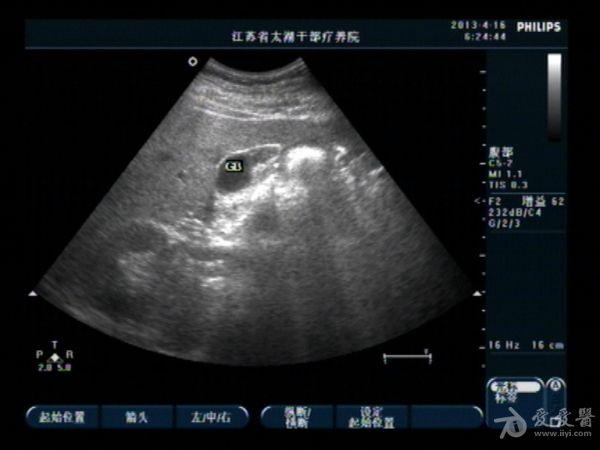

胆囊底部稍低回声区,胆泥沉积?胆囊癌不像吧?,请分析

男性,40,无右上腹痛